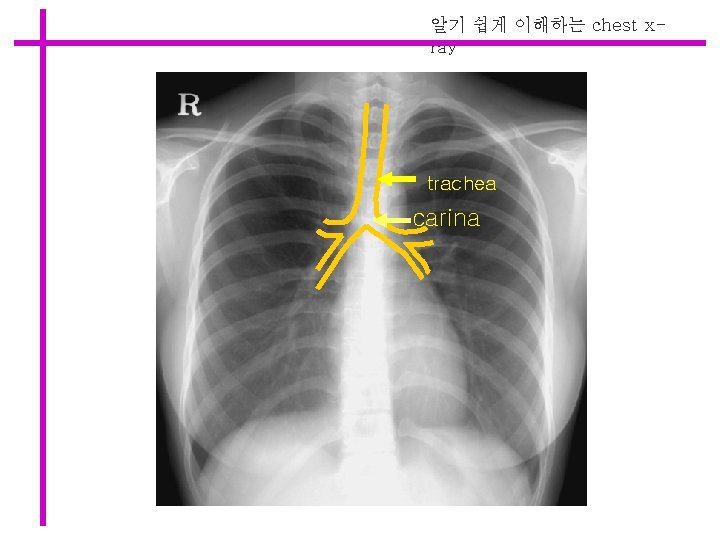

알기 쉽게 이해하는 chest xray trachea carina